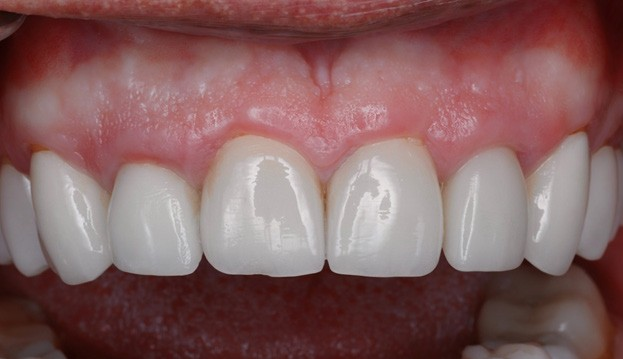

The 6 weeks follow up showed stable soft tissue, no signs of inflammation, and good maintenance by the patient. The implants showed no mobility and appeared to be integrating uneventfully.